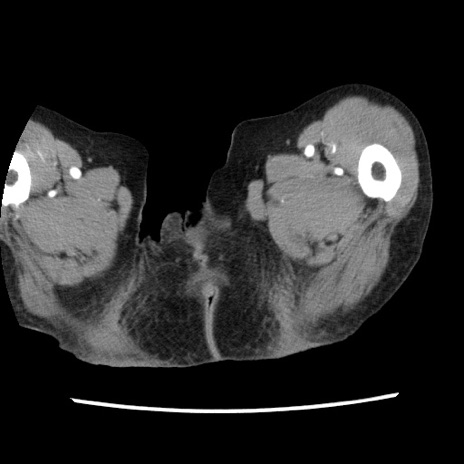

【症例】80歳代女性

【主訴】腹痛

【現病歴】8時間前から腹痛あり来院。

【既往歴】糖尿病、脂質異常症、子宮体癌にて子宮全摘術

【身体所見】意識清明・会話良好だが腹痛で苦悶様、全腹部にわたって反跳痛と圧痛あり

【データ】WBC 13600、CRP 0.14、LDH 224、CK 90